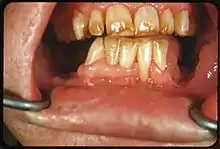

- جير الأسنان: هو تكلس لويحة الأسنان بعد اهمال تنظيفها، فهذا يؤدي إلى تشكيل رواسب صلبة على الأسنان، وخاصة حول اللثة. لون الجير قد يكون رمادي، أصفر، أسود أو بني.[4]

- التبغ: يميل القطران المتواجد بمنتجات التبغ إلى تشكيل بقع صفراء-بني- أوأسود حول أعناق الأسنان فوق خط اللثة.[5]

تلون الأسنان الخارجي

الصبغيات الخارجية شائعة، لها أسباب مختلفة وقادرة حتى على تلوين سطح الحشوات مثل حشوات الكمبوزيت الضوئية أو تيجان البورسيلين. عندما تبقى هذه التصبغات لفترة طويلة من الزمن على سطح الاسنان قد تصبح داخلية. هذه بعض المسببات للتصبغات الخارجية.